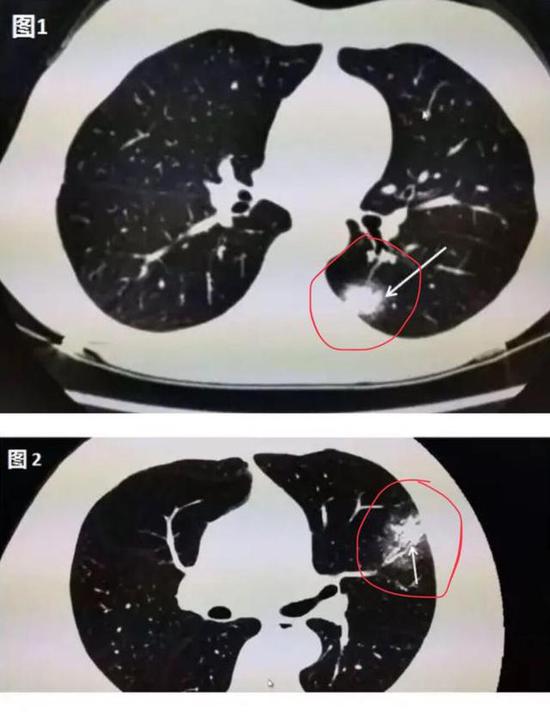

下圖是新冠肺炎患者在做肺部CT時的圖像,肉眼可見的紅色圈內或白色箭頭所指區域,相較于肺部其他正常部位出現了像云霧狀磨砂玻璃一樣的“病灶”,醫學上美其名曰“磨玻璃影”。

▲新冠肺炎患者肺部CT顯示磨玻璃影(圖片來自網絡)

其實,在疾病早期,肺部CT上可能并不會首先出現磨玻璃影。華中科技大學同濟醫學院附屬同濟醫院放射科管漢雄教授發文稱,患者一旦出現咳嗽、持續發熱、不明原因乏力時,CT常常會有陽性發現。肺部CT上可能出現一白色不規則的小斑片(如圖1箭頭所指區域),即“實變結節影”,或者是中央實變、周圍磨玻璃(如圖2箭頭所指區域),也就是中央區域是一白色不規則的小斑片,周圍則像云霧狀磨砂玻璃一樣。隨著病毒的持續“攻擊”,病情發展,感染加重,白色的實變結節區域開始吸收,如同一顆糖融化了一樣,慢慢變為磨玻璃影。

▲圖1:肺部CT上出現一白色的小斑片;圖2:中央區域是一白色的小斑片,周圍則像云霧狀磨砂玻璃一樣(圖片來自網絡)